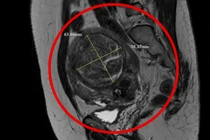

Nút mạch u xơ tử cung to như thai 6 tháng ở người phụ nữ tưởng bệnh mãn kinh

Nút mạch giúp can thiệp trực tiếp vào nguồn máu nuôi u, hạn chế tối đa chảy máu và tránh được các biến chứng tại ổ bụng.